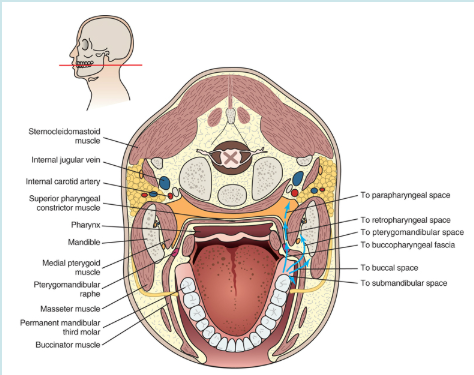

AS INDICATED BY THE BLUE ARROWS, an infection of what tooth type can spread to many potential spaces?

Mandibular molar